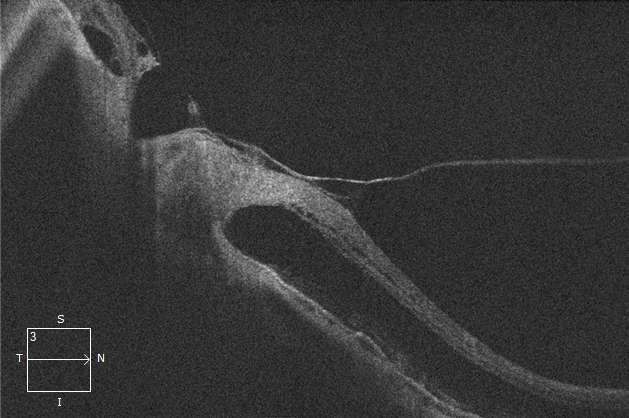

Imágenes aportadas por Dr. Cristian Sánchez

ü La degeneración macular relacionada a la edad es la causa más frecuente de pérdida de visión irreversible en personas mayores de 60 años

ü La patogenia es multifactorial, en que además del envejecimiento (principal factor de riesgo) los factores de riesgo genéticos y ambientales (Tabaquismo, obesidad abdominal) juegan un rol determinante

ü Su primera manifestación son las drusas sin embargo el proceso puede evolucionar a la forma seca o húmeda

ü La forma húmeda se caracteriza por la presencia de membrana neovascular coroidea que crece bajo el epitelio pigmentario y luego bajo la retina. Estos vasos de neoformación se originan en la coriocapilar, proliferan y penetran al espacio subepitelial a través de una ruptura de la membrana de Bruch

ü El desprendimiento de epitelio pigmentario puede preceder la neovascularización coroidea, y en ese caso su contenido es seroso, cuando se asocia a neovascularización coroidea su contenido es fibrovascular

ü Al examen oftalmoscópico, en caso de tener una membrana neovascular, se detecta un solevantamiento retinal, habitualmente redondeado y generalmente rodeado de un halo de sangre subretinal. El solevantamiento se debe a la presencia de líquido o edema retinal. La membrana neovascular puede ser extrafoveal, alejada del centro, pero en la mayoría de los casos es subfoveal

ü Una complicación inusual es la hemorragia subretinal masiva, lo que en algunos pacientes se asocia a terapia anticoagulante

ü Angiografía con fluoresceína en la membrana MNVC Tipo Ia (DEP fibrovascular): se caracteriza por presentar área hiperfluorescente irregular visible desde un tiempo arteriovenoso precoz que incrementa la fluoresceina en tiempos tardíos con poca o nula difusión

2.G. MEMBRANA NEOVASCULAR COROIDEA (MNVC)

Clement F . “Angiografía”. Diagnóstico por la imagen en la retina, Sociedad Española de Retina y Vítreo, editado por Ignasi Jügens, Elservier, 2014, pp 41-66 Juan Verdaguer, T. (2010). Degeneración macular relacionada a la edad. Revista Médica Clínica Las Condes, 21(6), 949–955. doi:10.1016/s0716-8640(10)70620-9

A B